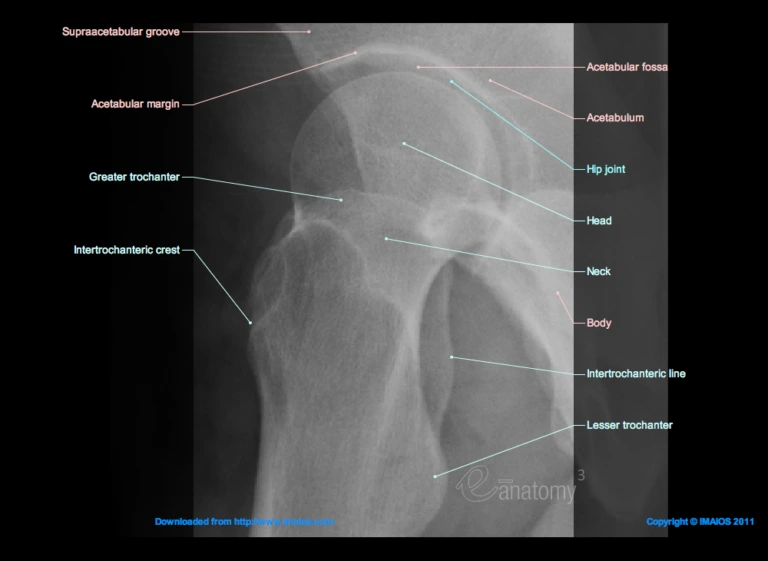

The hip joint is a large joint where the leg joins the pelvis, functioning as a ball and socket joint. The top of the thigh bone (the femur) is a round ball, which fits into the socket formed by a cavity in the pelvic bone. The ball is held in the socket by a grouping of ligaments that form a capsule around the joint. This capsule of ligaments contains a lubricating synovial fluid and cartilage, which allows the two bones to move against each other with minimal friction.

II. The Hip Joints

The Hip Joints contain joint fluid and are lined by cartilage.